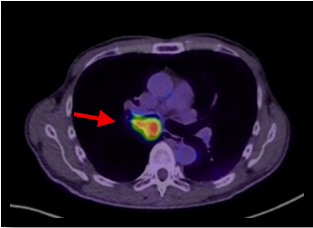

肺がん原発巣の症例。(病変部は赤矢印)

PET画像 → 解剖部位がわかりにくい

PET画像とCT画像を重ね合わせることで、病変が存在する解剖部位が分かるため診断能が高くなる